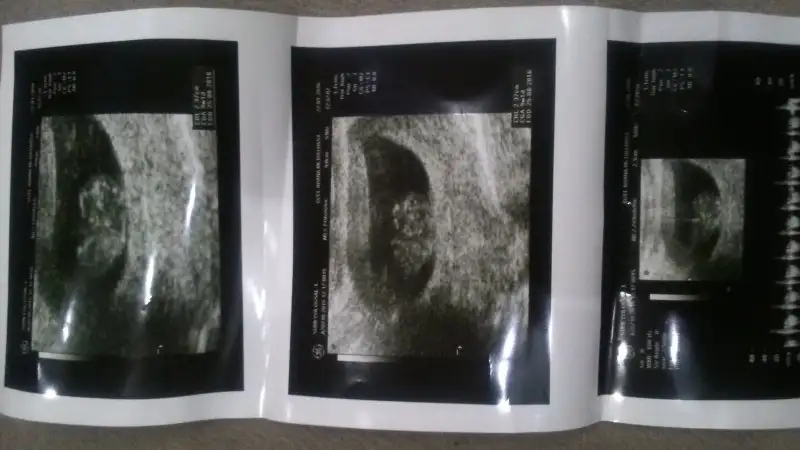

Şimdi Size Son ultrason resmimizi atayım bi maşallah alırız :)

Evet senin meleğin de böyle olacak inşallah annesi :)kocaman maşallah onaartık çok net belli. Aramızda 4 hafta var yaklaşık ve 4 haftada bu kadar büyüyeceğini düşünmemiştim. Sen çok net hissediyorsun ya, bence de kız. Bu arada iki rüya gördüm, cumartesi hayırlı haberler alırsam anlatıcam size.

Gerçekten büyümüş silüeti cok rahat görünüyor maşallahAynen canım yormamaya çalışıyorum ama akşamları öyle yorgun düşüyorum ki yazdıklarınızı okuyorum ama kafayı toplayıp bi türlü yazacaklarimi toparlayamiyorum isyan edip çıkıyorum :) bedensel bi aktivite yok sayım yapılıyo ben bilgisayardan çalışıyorum ama sanki tırâ mal yüklemiş gibi yorgun oluyorum

Evet canım artık yavaş yavaş bebeğe benziyo:)Gerçekten büyümüş silüeti cok rahat görünüyor maşallah